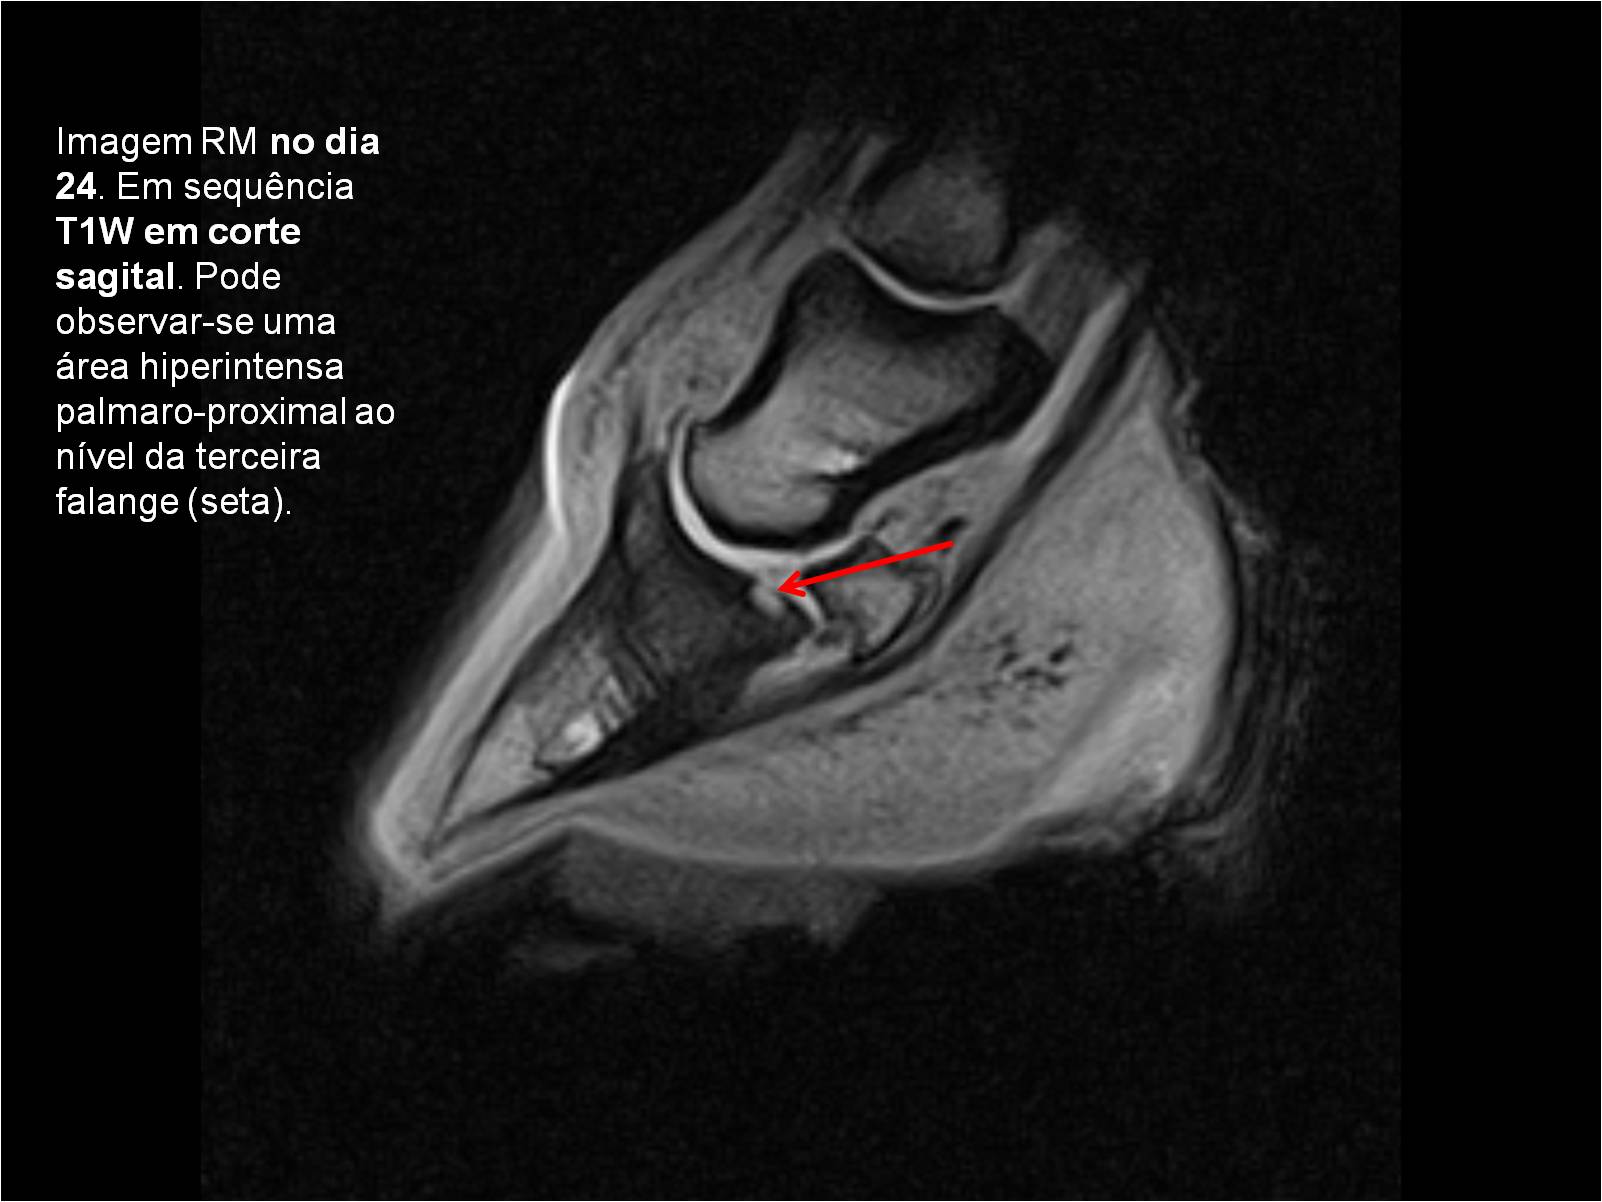

Publisher: Universidade de Évora

Abstract: O relatório de estágio encontra-se estruturado em três partes distintas. A primeira parte faz a caracterização das infraestruturas e funcionamento do Hospital Veterinário de Equinos de Lüsche, Oldenburg, Alemanha, assim como a análise casuística dos casos clínicos acompanhados durante os 6 meses de estágio. A segunda parte consiste de uma revisão bibliográfica sobre quistos do osso subcondral em equinos. Por fim, a terceira parte consta da apresentação e discussão de um caso clínico, nomeadamente o diagnóstico e acompanhamento imagiológico, por ressonância magnética, de um quisto subcondral na terceira falange num cavalo adulto; ### Abstract Equine Practice- Subcondral bone cyst of the third phalanx This internship report is divided in three parts. The first part characterizes the infrastructure and function of the Equine Hospital Lüsche, Oldenburg, Germany, as well as the casuistic of the clinical cases accompanied during the 6 month internship. The second part consists in a bibliographic review of cystic lesions of the subchondral bone in equines. The third part consists in a case report, the diagnostic and imagiological accompaniment, by use of magnetic resonance imaging, of a subchondral bone cyst in the distal phalanx of an adult equine.